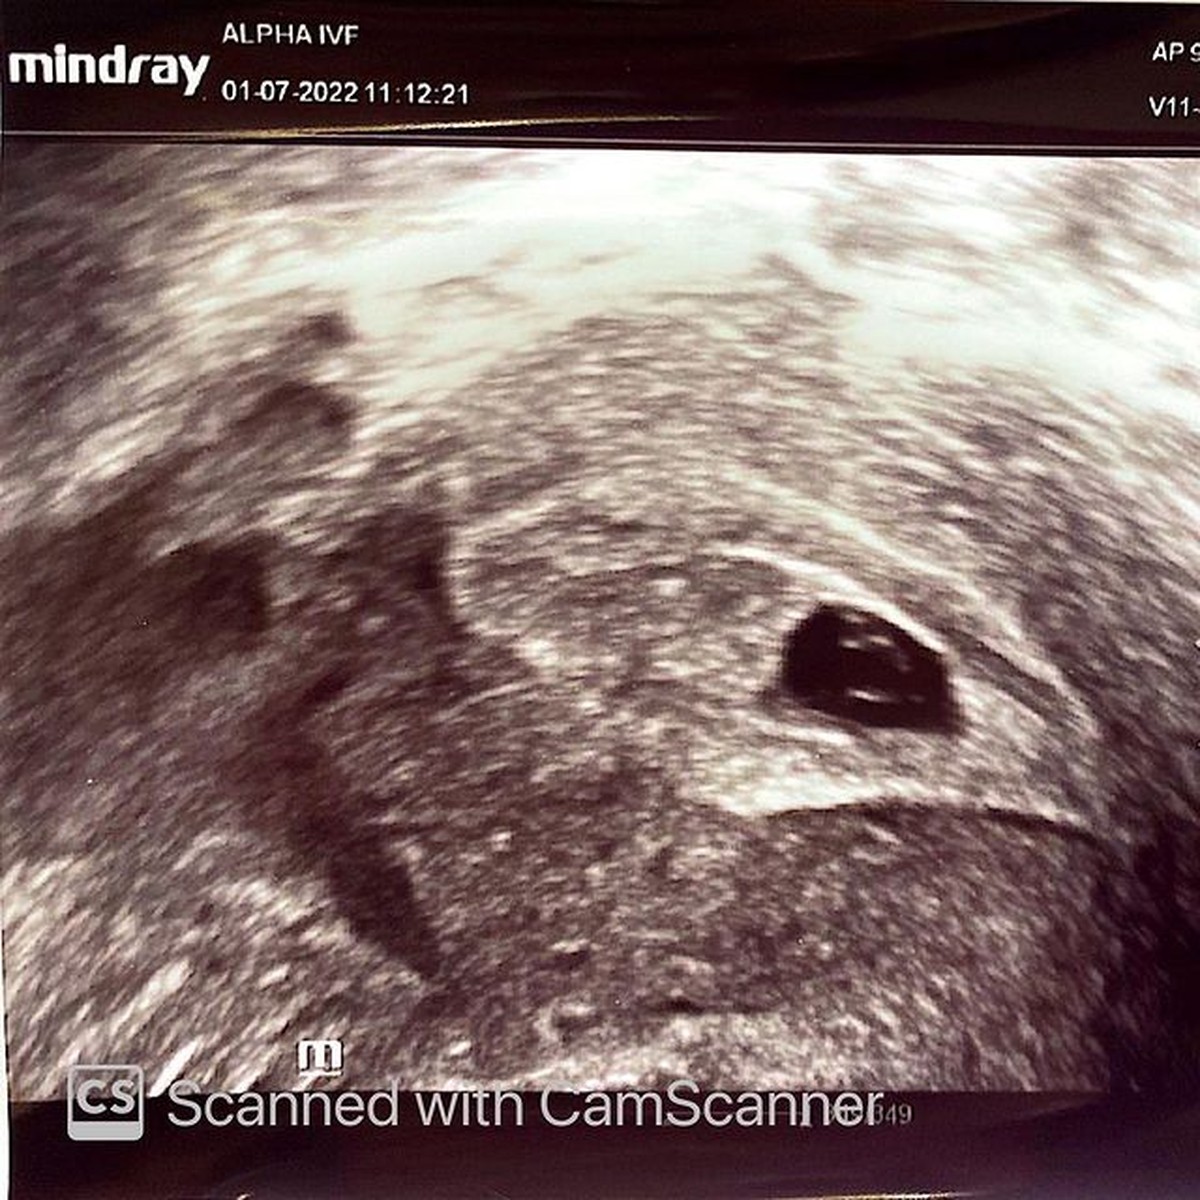

Namun saat memasuki usia kandungan 7 minggu, Annisa dinyatakan mengalami keguguran.(Foto: instagram.com/annisayudhoyono)

Janin Annisa tidak berkembang, detak jantungnya belum ada hingga ukuran bayi yang ada diperutnya terlalu kecil.(Foto: instagram.com/annisayudhoyono)

Hal ini pun membuat Annisa harus menjalani operasi dengan sistem Oprac untuk mengeluarkan janinnya.(Foto: instagram.com/annisayudhoyono)